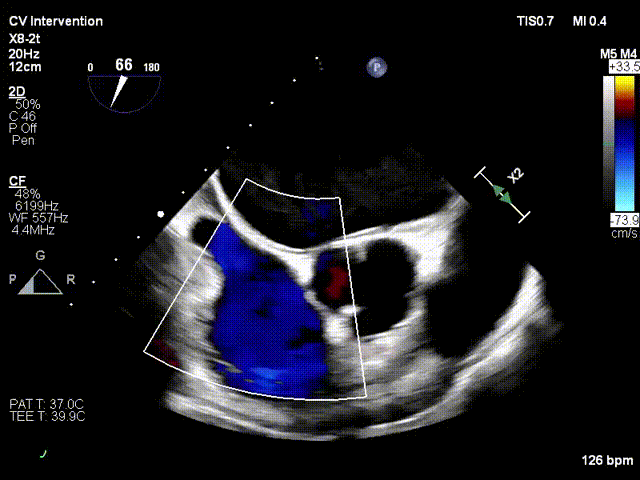

Ultrasound Evaluation: Severe tricuspid insufficiency (mean vena contracta 9mm), with the regurgitation orifice located at the anteroseptal commissure. The mechanism of regurgitation is myxomatous degeneration of the valve leaflets, accompanied by poor leaflet coaptation or reduced coaptation height. The mean diameter of the tricuspid annulus is 37mm. Echocardiographic evaluation confirmed that the anatomical structure is suitable for the K-Clip® system.

After the patient was placed under general anesthesia, the jugular vein was punctured intraoperatively to establish surgical access. An 18Fr delivery sheath was advanced along a stiff guidewire to the mid-inferior right atrium, and the delivery system was introduced under ultrasound guidance. A 12T K-Clip® device was implanted at the posterior annulus, and another 12T K-Clip® device at the anteroposterior annulus respectively. The angle between the device and the annulus plane was adjusted through catheter deflection and rotation, directing the tip of the clip device to the target position. The anchoring component was deployed into the annulus under ultrasound MPR mode; after confirming stable traction, the clamping arms were opened and apposed to the annulus, followed by retraction of the anchoring component to close the clamping arms for annuloplasty. The surgical effect was evaluated as satisfactory, and the clip components were then released.

Deployment of the anchoring component under the MPR view

Opening the clamping arms, adjusting the direction and apposing to the annulus

After implanting one 12T K-Clip® device at the commissure of the posterior and septal leaflets of the tricuspid valve and another 12T K-Clip® device at the commissure of the posterior and anterior leaflets, the overall area of the tricuspid annulus was reduced. Tricuspid regurgitation was decreased from severe (4+) preoperatively to moderate (2+), the regurgitation was effectively alleviated, the surgical effect met the expected goals, and the surgery was successfully completed.